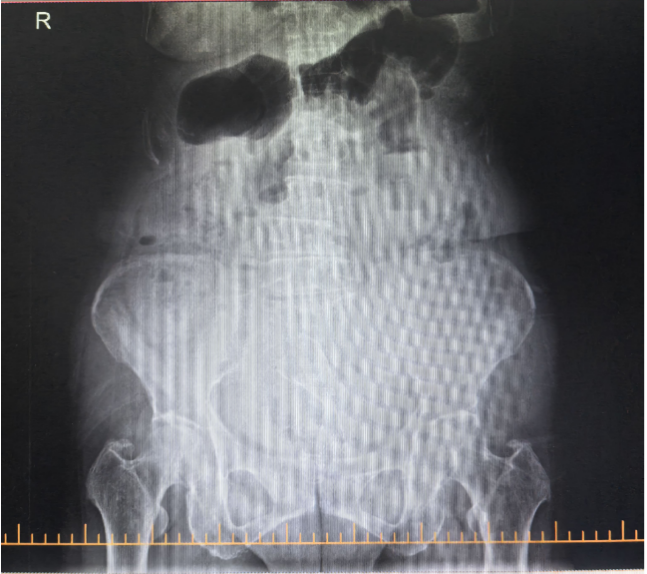

治療前腹CT示腸腔明顯擴張 治療后立位腹平片示腸道梗阻較前明顯緩解